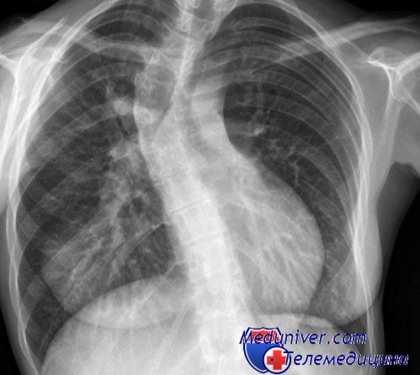

Тяжелое искривление позвоночника влияет на функции внутренних органов: нарушает механику дыхания, снижает насыщение артериальной крови кислородом, вызывает нарушение кровообращения в малом кругу и способствует к гипертрофии миокарда правой половины сердца, то есть развитию симптомокомплекса легочно-сердечной недостаточности, объединенного названием "кифосколиотическое сердце".

Характерные симптомы грудного кифосколиоза - боль в спине, головокружение, быстрая утомляемость и одышка при физических нагрузках. При кифосколиозе из-за плохой подвижности грудной клетки увеличивается нагрузка на дыхательные мышцы, уменьшается растяжимость паренхимы и функциональная остаточная емкость легких. Из-за снижения легочных объемов нарушается газообмен, что и становиться причиной развития легочной недостаточности. У больных даже с умеренной деформацией грудной стенки кифосколиоз приводит к лёгочной гипертензии и одышке при физической нагрузке. Длительная гипоксемия дает осложнение на сердце, нарушается работа правого желудочка сердца и развивается кифосколиотическое (легочное) сердце.

Из-за кифосколиоза ограничивается подвижность грудной клетки и диафрагмы. Это приводит к увеличению нагрузки на дыхательные мышцы, снижению растяжимости легочной паренхимы и уменьшению функциональной остаточной емкости легких. В результате уменьшается объем легких, нарушается газообмен: в крови становится больше углекислого газа и меньше кислорода. При выраженном кифосколиозе возникает видимая деформация грудной клетки, влекущая за собой еще более значимые нарушения функции легких и сердца.